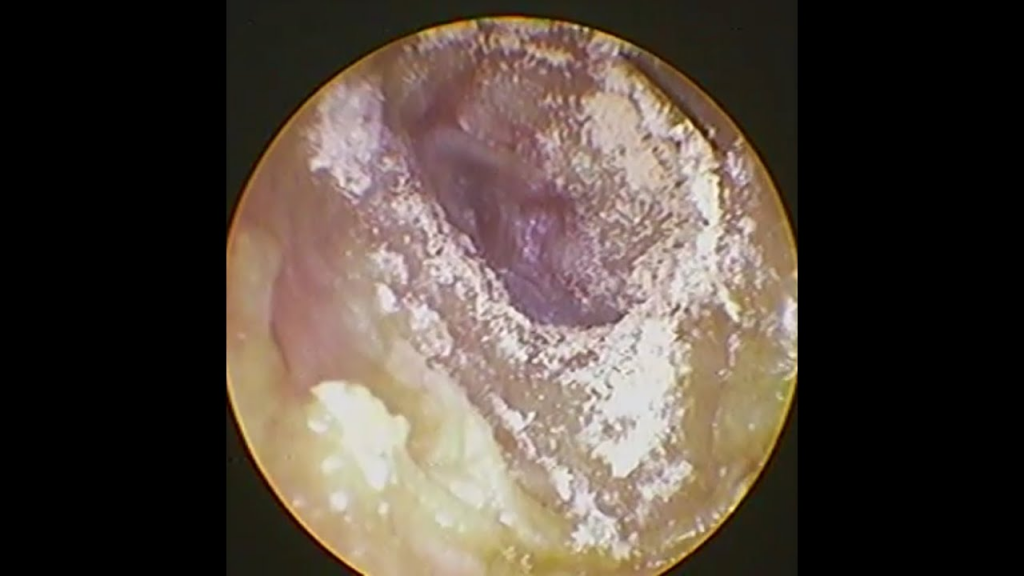

Dấu hiệu của nấm tai

- Ngứa tai rất nhiều

- Cảm giác tai ẩm hoặc có mùi nhẹ

- Có thể xuất hiện mảng trắng, đen hoặc vàng trong tai

Nấm tai thường gặp ở những người thường xuyên bơi lội, tai ẩm lâu hoặc sử dụng tai nghe trong thời gian dài.